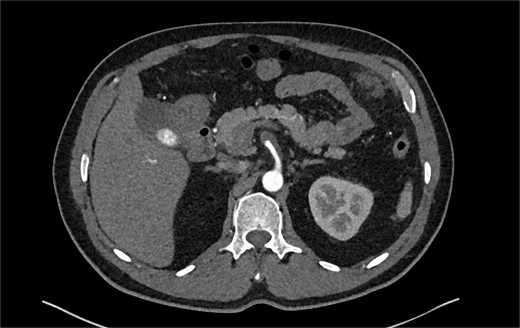

A 60-year-old male with a past medical history of hypertension presented to our emergency department with 45 minutes of severe abdominal pain accompanied by nausea and vomiting. The patient’s presenting blood pressure was 192/130 mmHg with a heart rate of 77 bpm, and the remaining vitals were within normal limits. On physical examination, tenderness was noted in the epigastric region without peritoneal signs. A CT of the abdomen and pelvis revealed a partial thrombosis of the SMA, extending into some of the mesenteric branch arteries, with no evidence of bowel ischemia. The patient was started on a high-dose heparin drip. A same-day repeat CT angiogram further indicated 75% SMA stenosis secondary to SMA dissection with thrombosis of the false lumen (Fig. 1).

CTA abdomen and pelvis demonstrating 75% SMA stenosis secondary to SMA dissection with thrombosis of the false lumen.